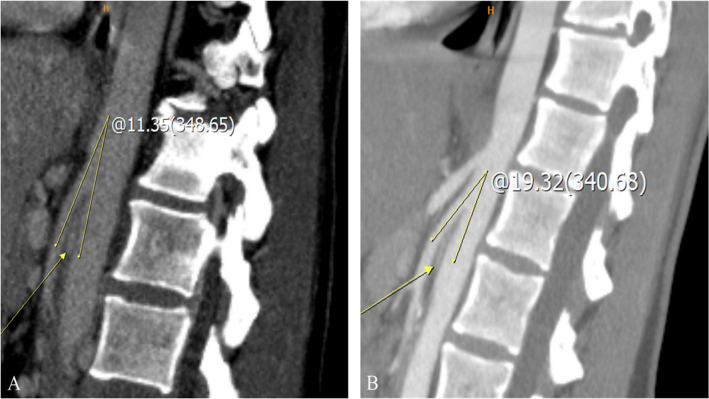

胡桃夹子综合征(NCS)是一种相对罕见的血管疾病,其特征是左肾静脉(LRV)受压,导致多种非特异性症状,包括血尿、侧腹疼痛、精索静脉曲张和盆腔充血综合征。LRV受压来源可分为前、后两种:前路NCS发生于LRV受压于主动脉与肠系膜上动脉之间,后路NCS发生于主动脉与脊柱之间。尽管诊断方式有了进步,包括多普勒超声、计算机断层扫描、磁共振成像和侵入性技术,如静脉造影术,但仍然没有全球公认的诊断算法,导致诊断不一致。此外,由于缺乏标准化的治疗指南,前路NCS的最佳治疗仍然是一个有争议的话题。虽然在儿童人群中通常推荐保守治疗,但侵入性治疗——包括LRV转位和肾脏自体移植等手术选择,以及介入放射治疗(如支架置入术)——存在支架移位、再狭窄和材料长期耐用性等挑战。尽管如此,3d打印支架的出现为患者特异性治疗提供了潜在的改进,特别是在儿科人群中,但其临床疗效和安全性仍在调查中。本文简要介绍了目前关于前路NCS治疗的讨论,强调需要标准化的诊断算法、多学科方法和持续的技术进步来完善治疗可能性和策略。进一步的研究对于解决这些争议和就最佳做法达成共识至关重要。

Nutcracker syndrome (NCS) is a relatively uncommon vascular condition characterized by compression of the left renal vein (LRV), resulting in a variable spectrum of nonspecific symptoms, including hematuria, flank pain, varicocele, and pelvic congestion syndrome. NCS can be classified into anterior and posterior types regarding the origin of LRV compression: anterior NCS occurs when LRV is compressed between the aorta and superior mesenteric artery, whereas posterior NCS involves LRV compression between the aorta and the spine. Despite advancements in diagnostic modalities, including Doppler ultrasound, computed tomography, magnetic resonance imaging, and invasive techniques like phlebography, there is still no globally accepted diagnostic algorithm, leading to inconsistencies in diagnosis. Moreover, due to the lack of standardized treatment guidelines, the optimal management of anterior NCS remains a topic of debate. While conservative management is usually recommended in the pediatric population, invasive treatments-including surgical options like LRV transposition and renal autotransplantation, as well as interventional radiology procedures like stenting, present challenges such as stent migration, restenosis, and long-term material durability. Nevertheless, the emergence of 3D-printed stents offers potential improvements in patient-specific treatment, particularly in the pediatric population, yet their clinical efficacy and safety remain under investigation. This brief communication addresses the current discussions regarding anterior NCS management, emphasizing the need for standardized diagnostic algorithms, a multidisciplinary approach, and continued technological advancements to refine treatment possibilities and strategies. Further research is critical to resolve these controversies and establish a consensus on best practices.